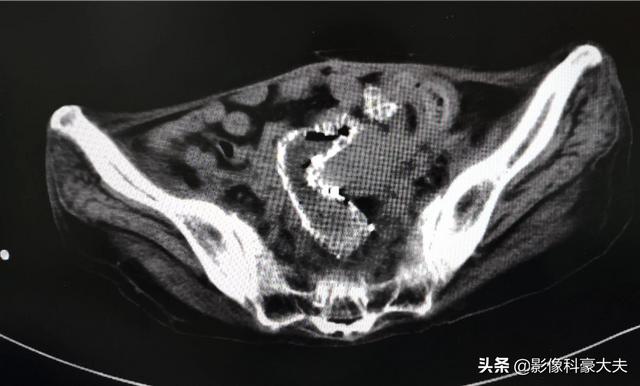

この女性も、手術不可能な進行大腸がんを患った中年女性だったが、腸閉塞があり、放っておけばすぐに窒息死するところだった。そこで妥協案が出され、大腸にステントを留置して腸の問題を解決し、少なくとも数カ月から数年は延命することができた。